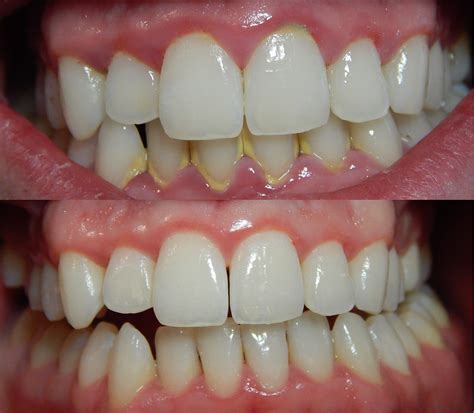

Before understanding what gingivitis looks like, it's essential to know what healthy gums should look like. Healthy gums typically appear pale pink in color, firm to the touch, and fit snugly around each tooth. They have a stippled texture similar to an orange peel and don't bleed during normal brushing or flossing. The gum line should be even and consistent, creating a smooth seal around the teeth.

When gingivitis develops, these characteristics change noticeably. The most obvious visual sign is a change in color—gums affected by gingivitis often appear red or dark red, sometimes even purplish in severe cases. This redness is caused by increased blood flow to the inflamed tissue. The gums may also look shiny or glossy rather than having their normal matte appearance, and they lose their firm texture, becoming soft and puffy instead.

• gingivitis pictures before after